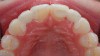

The few available adhesive systems of the 1970s and early 1980s were relatively hydrophobic in nature and unable to adequately penetrate the dentin smear layer, thus limiting their direct interaction with the tooth tissues. The smear layer is the residue that is left on the surface of the dentin after rotary instrumentation with diamond or carbide burs (Figure 1). It is a thin amorphous layer largely composed of degraded collagen, bacteria, and various inorganic dentin and enamel debris.6,7 Early adhesive systems were extremely limited and generally ineffective, in part because they bonded directly to the smear layer and were, thus, limited by the smear layer’s low intrinsic cohesive strength.8 Eventually, it was recognized that the smear layer needed to be removed and/or modified and bypassed in some fashion so that adhesive primers and resins could interact directly with the dentin. In the case of total-etch adhesive systems, the smear layer is essentially dissolved with phosphoric acid (H3PO4) and subsequently washed away during the rinsing step (Figure 2 and Figure 3). With self-etching systems, various acidic primers are used to modify, disrupt, and/or solubilize the smear layer and, although the remnants are not washed away as with total-etch systems, still permit direct adhesive interaction with the dentin substrate.9

Typical “peanut butter spread on toast” appearance of the dentin smear layer. (SEM courtesy of Jenny Wang.)

Figure 1